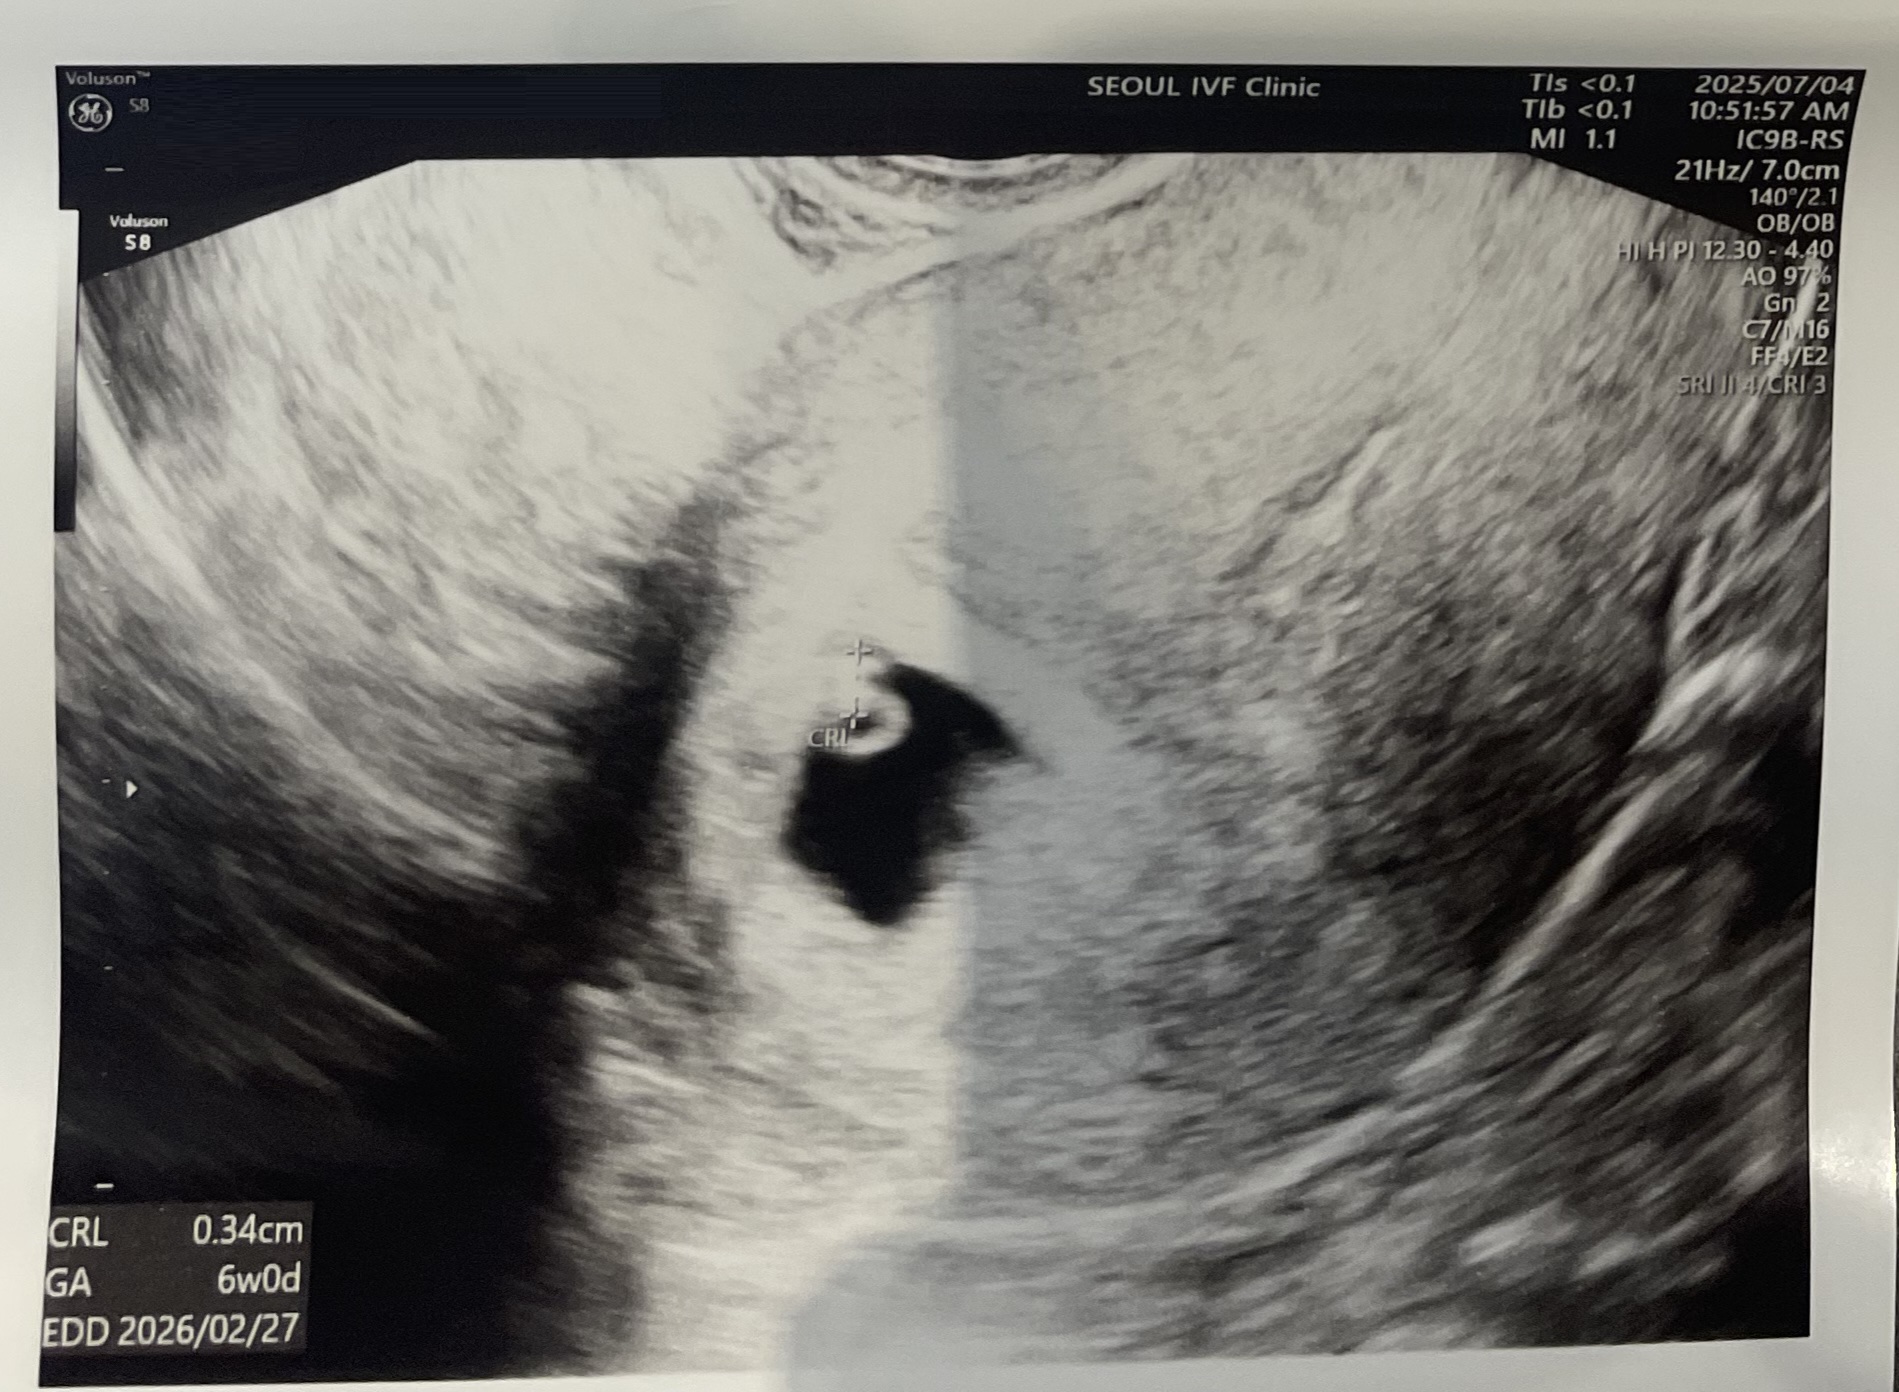

| 치료 도중 느꼈던 가장 기뻤던 순간과 절망적인 것들은 무엇인가요? 잊지 못할 경험이 있나요? | 가장 기뻤던 순간은 초음파에서 아기집을 처음 확인했을 때였습니다. 말로 다 표현할 수 없는 감동이 밀려왔습니다. 반대로 가장 불안하고 절망적이었던 순간은 6주까지 이어진 선홍빛과 갈색빛 출혈이었습니다. 혹시 잘못될까 마음을 졸이며 지냈지만, 다행히 잘 이겨내고 지금까지 올 수 있었습니다. |